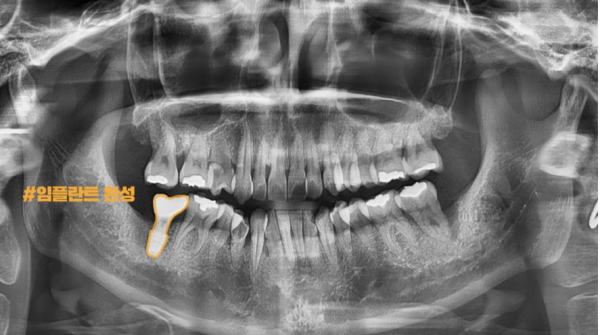

이 환자분은 양쪽 아래 어금니에 염증이 생겨 잇몸뼈가 녹은 상태였습니다.

모두 상태가 좋지 않아 발치를 하고 임플란트를 하게되었고 디지털임플란트의 첫 단계인

구강스캔, CT촬영, 엑스레이 등을 통해 정확히 진단하고 모의수술을 하게됩니다.

This patient had inflammation in both lower molar teeth and melted gum bones.

They were all in bad condition, so they had to have their teeth extracted and implants done, and that's the first step in digital implants.

It is accurately diagnosed and simulated through oral scans, CT scans, and X-rays.